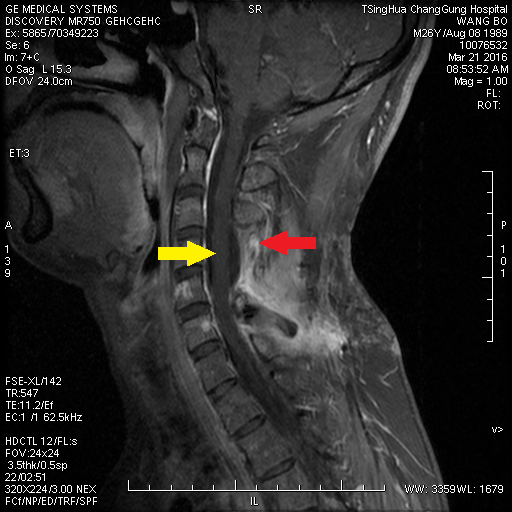

清华长庚医院手术直播:成功挑战脑干及高颈髓禁区肿瘤手术